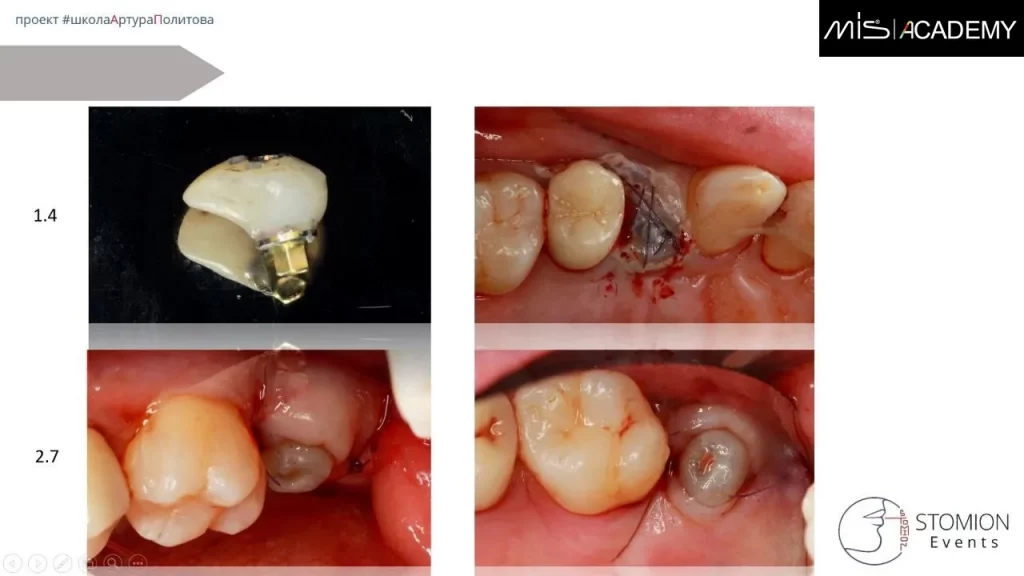

- Удаление 1.4.

- Одномоментная имплантация в нёбный корень MIS C1 3,75×11,5.

- СТТ с бугра вестибулярно.

- Коннект абатмент, индивидуальный ФДМ для создание клапана и первичного заживления.

Параллельно установлен имплантат MIS C1 5×8 в позиции 2.7.

С уровня имплантата выполнена реставрация с цементной фиксацией на индивидуальном абатменте.